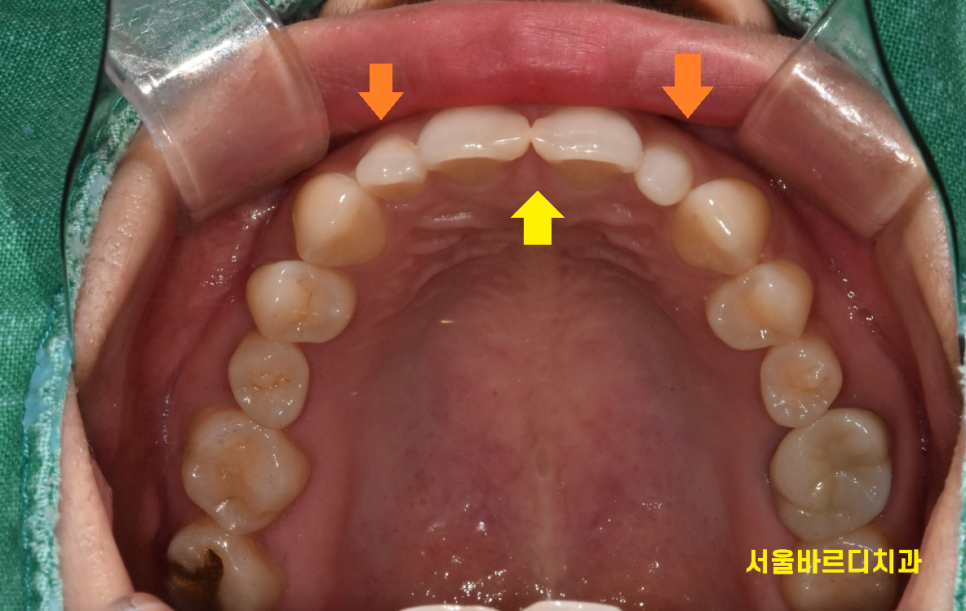

왜소치 라미네이트 제작을 위해

치아를 삭제한 사진입니다.

아래 치아는 건들이지 않은 자연치

윗니의 경우 치아를 삭제했는데

두께가 크게 달라지지 않은 것을 보실 수 있을겁니다.

(최소한만 삭제하여 치아를 아껴줍니다!!)

너무 큰 치아는 사이즈를 줄여주고

왜소치 같은 경우 크기를 키워주고

원하는 크기만큼 보철을 만들어주어

기존 치아 위에 붙여 덮어주는 방식으로